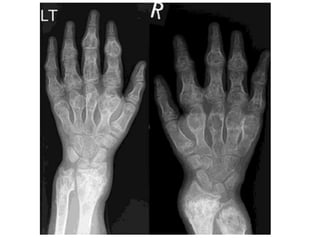

• On X-ray, the chondromas can be very large with

consequent expansion of the bone, thinning of

the cortex or, indeed, no cortex at all (Figure 9.14).

• In Maffucci syndrome, the presence of haemangioma

may be seen on imaging by phleboliths.

• Histologically, the chondromas appear more cellular

than solitary chondromas, with more proliferative

potential.

• Transformation to a secondary sarcoma is seen in both

these conditions.

• In Ollier’s disease, this may occur in 20–30% of

patients; in Maffucci syndrome, this is much more

common and is likely to be greater than 50%.

MULTIPLE CHONDROMAS AND ASSOCIATEDCONDITIONS • In Ollier’s disease, multiple chondromas may be found within the hand of one limb, or have a much wider, hemisomic distribution, or affect the entire body with a hemisomic prevalence. • The disease is non-hereditary and sporadic. • It most commonly affects the tubular bones of the hand or foot. • Chondromas normally present as bony swellings in childhood which may cause deformities and limb length discrepancy due to epiphyseal fusion anomalies.

• 39.

• In Maffuccisyndrome, multiple chondromas are associated with multiple cutaneous or deep haemangiomas. • On X-ray, the chondromas can be very large with consequent expansion of the bone, thinning of the cortex or, indeed, no cortex at all (Figure 9.14). • In Maffucci syndrome, the presence of haemangioma may be seen on imaging by phleboliths. • Histologically, the chondromas appear more cellular than solitary chondromas, with more proliferative potential. • Transformation to a secondary sarcoma is seen in both these conditions. • In Ollier’s disease, this may occur in 20–30% of patients; in Maffucci syndrome, this is much more common and is likely to be greater than 50%.